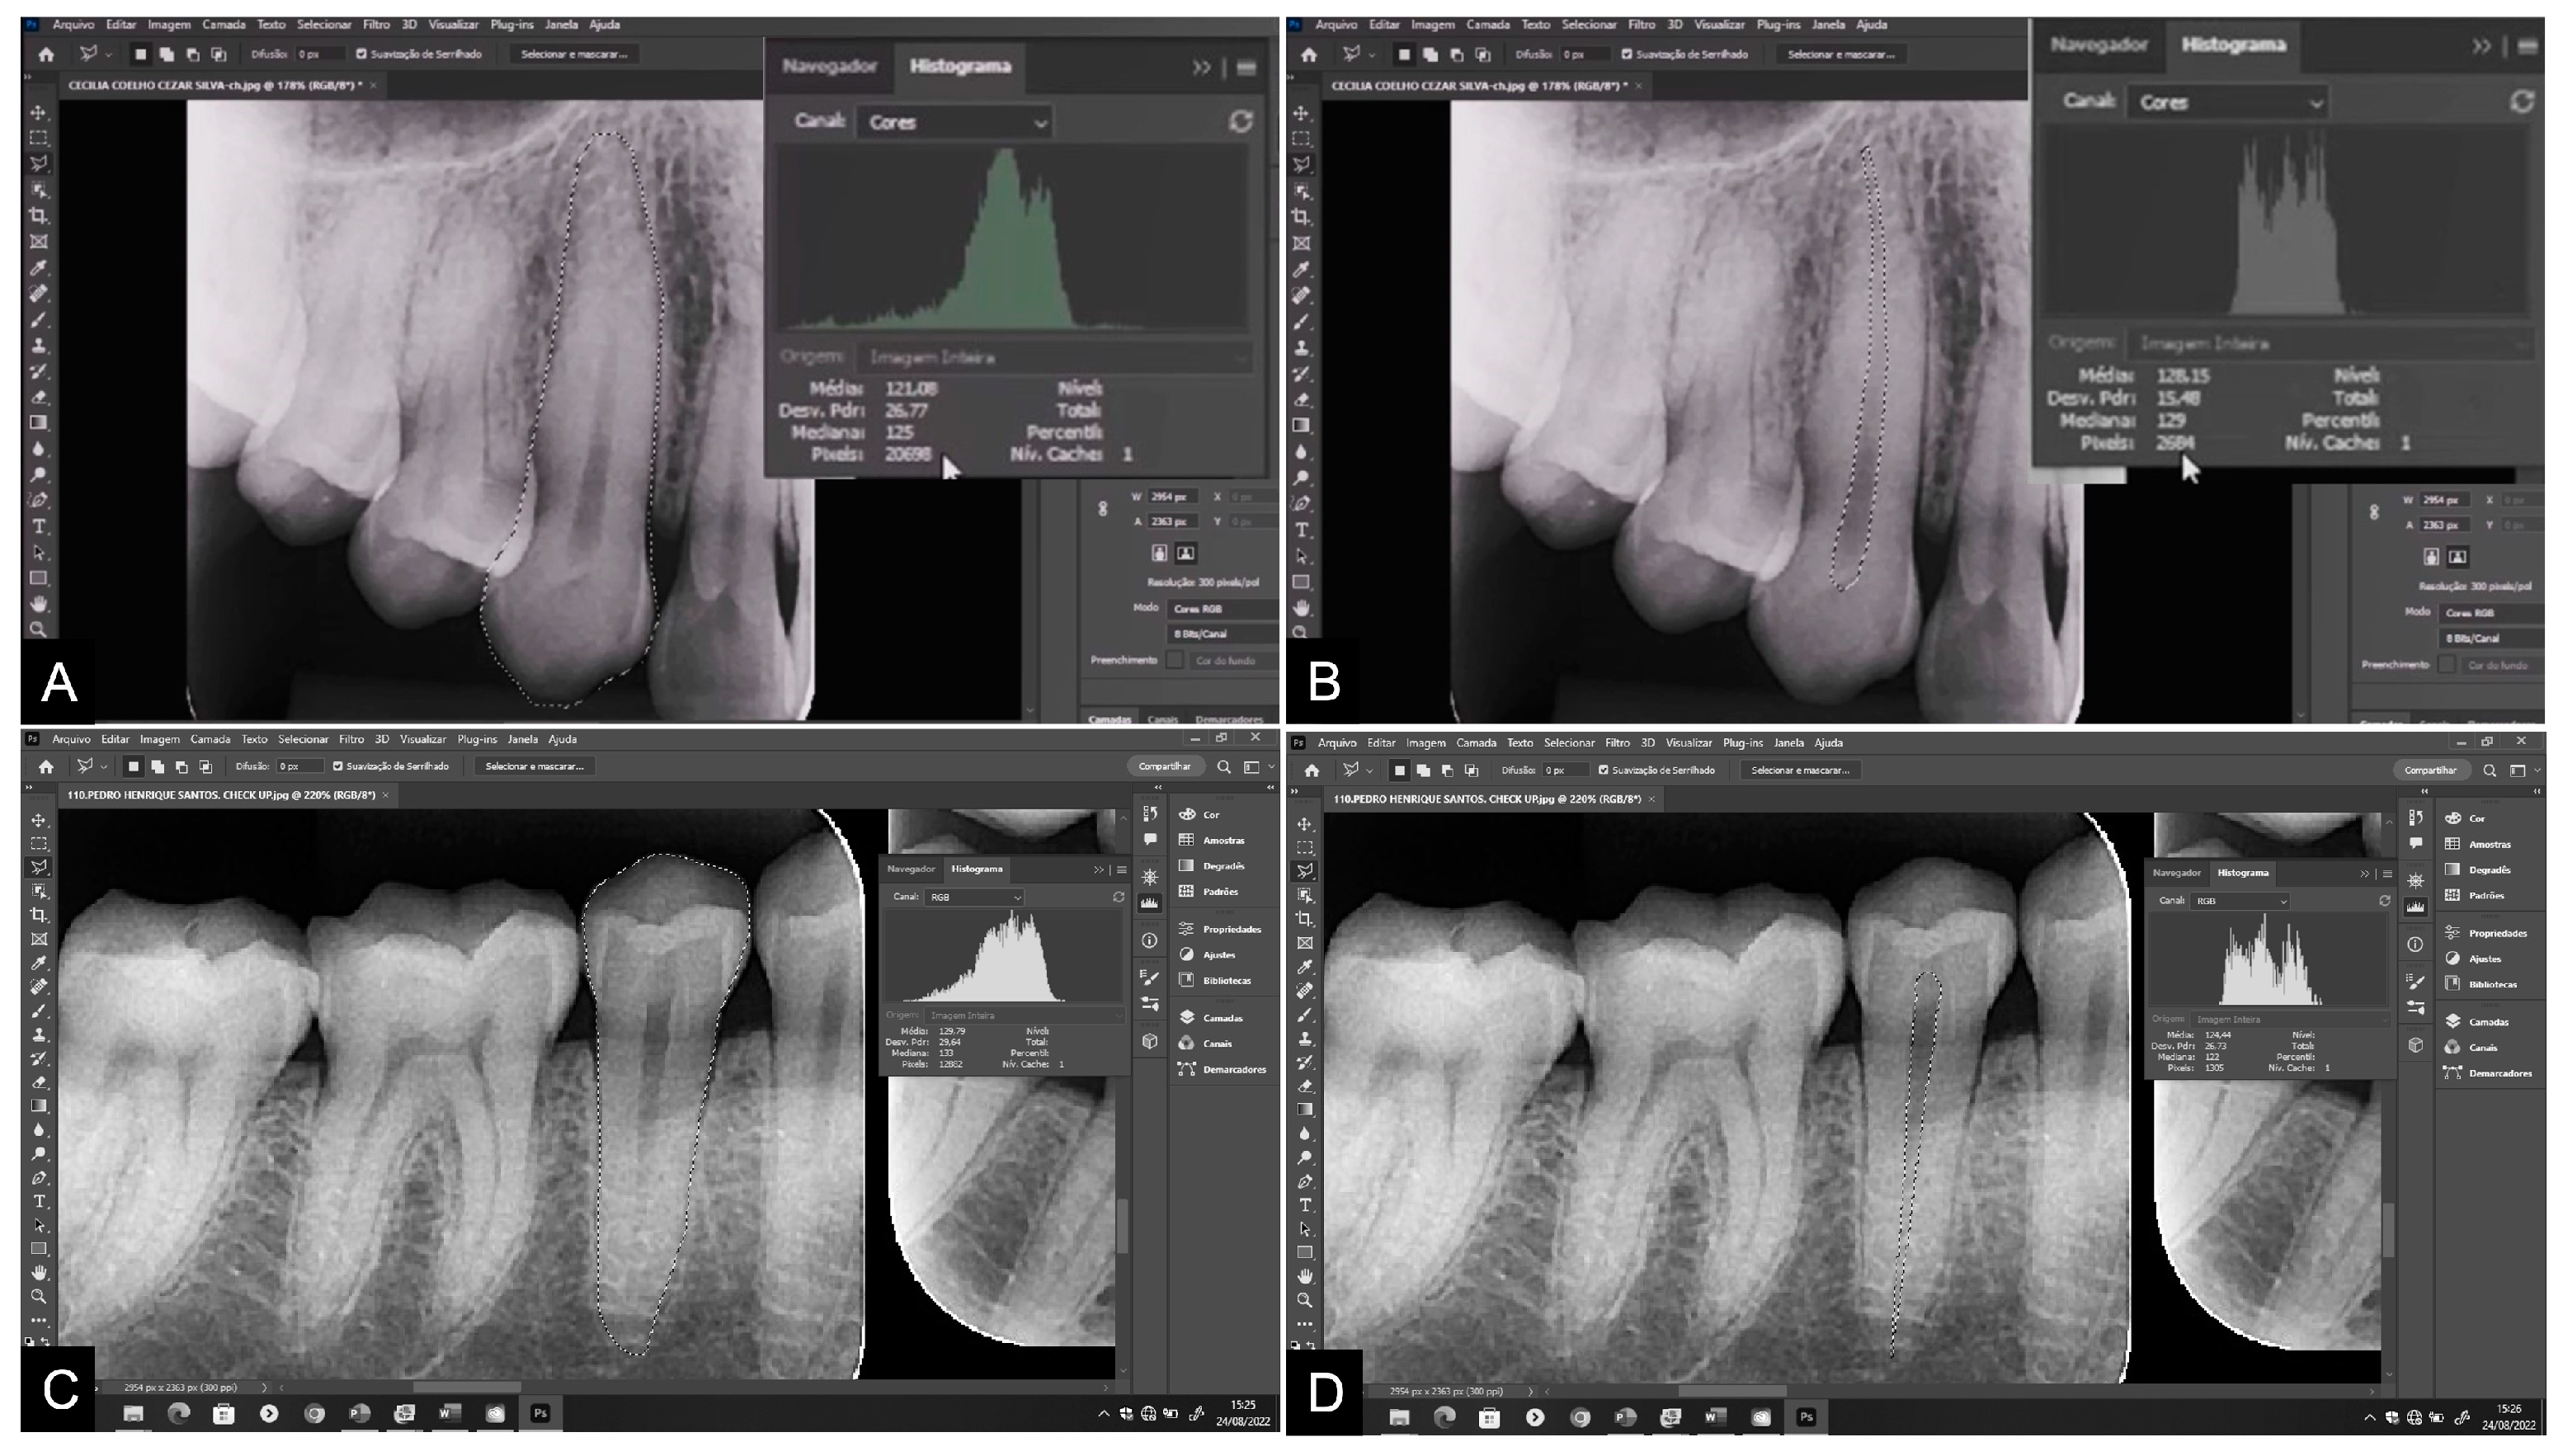

2. Materials and Methods